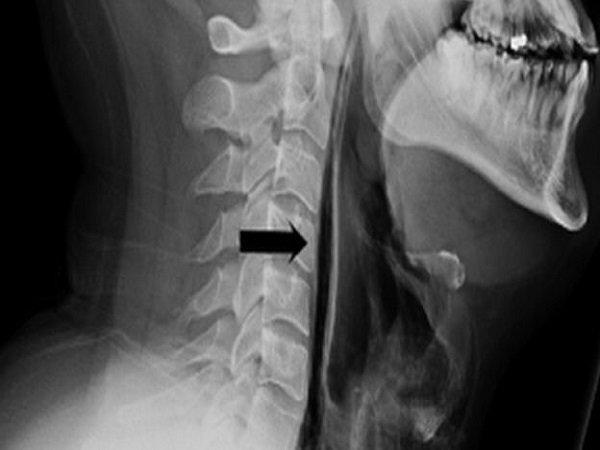

அது மட்டுமல்லாமல் தொண்டையில் ஏற்பட்ட துளை வழியாக நான் சுவாசிக்கும் காற்று செல்லும் போது ஒரு வெடிக்கும் சத்தமும் எனக்கு கேட்டது. மருத்துவர்கள் அவரை பரிசோதித்து இந்த வெட்டிக்கும் சத்தம் ஏர் பப்பிள்ஸ்களால் ஏற்படுகிறது என்பதையும் கண்டறிந்துள்ளனர். மேலும் மருத்துவர்கள் அவரது தொண்டையில் ஏற்பட்டுள்ள துளைக்கும் சிகிச்சை அளிக்க முற்பட்டுள்ளனர்.

இதற்காக ஒரு நீட்டமான குழாயை அவரது வாயின் வழியே விட்டு அதன் வழியாக உணவு, ஆன்டி பாயோடிக்ஸ் மருந்துகள் செலுத்தப்பட்டது. ஒரு வார காலமாக அவருக்கு சிகிச்சை அளிக்கப்பட்டு உள்ளது. மேலும் இனி மேல் தும்மல் வந்தால் அடக்க கூடாது என்றும் அவருக்கு எச்சரிக்கை செய்து மருத்துவர்கள் அனுப்பி உள்ளனர்.